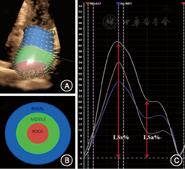

3D–mechanics软件将左房全容积图像切分显示为多切面(同前),软件默认将左房壁按左室16节段划分。根据解剖结构特点我们将左房划分为基底(Basal)、中间(Middle)、房顶(Roof)三部分(分别对应16节段基底、中间和心尖部)(图2),调整图像使三部分划分更接近其空间构型。LAES为时间起点,LAED、LAES帧手动描记左房内膜边界后软件自动追踪其运动轨迹,逐帧观察调整。左房三部分形变以三维速度向量(VVI)模式和应变曲线显示(图2),调整显示模式和时间间期,计算获取参数。主要参数:左房基底、中间、房顶部和整体(Global)心室收缩期长轴峰值应变(LSs%)和心房收缩前长轴峰值应变(LSa%),分别记为BLSs、MLSs、RLSs、GLSs和BLSa、MLSa、RLSa、GLSa(图2)。整体应变为三部分应变均值。在3D–STE基础上,参考既往研究[8]引入左房僵硬指数(LA stiffness index),其定义为E/Ea与GLSs%比值,数值越大表明左房僵硬度越高,顺应性越低。

LSs参数中,MLSs、GLSs具满意可重复性(ICC>0.8,0.89和0.82),BLSs、RLSs的ICC为0.71、0.61,观察者间一致性Bland–Altman分析见图3。LSa参数MLSa、GLSa、BLSa、RLSa的ICC分别为0.81、0.78、0.71和0.57。

HFpEF左房功能变化及意义,心动周期中,左房功能按时相可分为充盈期(储备功能),被动排空期(通道功能))和主动排空期(泵功能)。左房充盈期形变LSs主要受左室收缩牵拉、左房主动松弛和僵硬度的影响[10]。虽然射血分数在正常范围,但Morris等[11]研究发现HFpEF患者左室收缩形变已明显减低。研究入组排除了房颤和明显二尖瓣反流等瓣膜病患者,故E/Ea可较好反映左房充盈压力变化,而GLSs%与左房充盈容量明显相关。因此在既往研究基础上我们引入左房僵硬度的3D–STE无创评估指标:定义为E/Ea与GLSs%的比值。研究结果表明HFpEF患者左房充盈期形变明显减低,形变与左房大小明显负相关,左房明显增大前形变减低以中间部为主,随左房进一步增大,除中部外,基底和房顶部形变功能也出现显著下降。HFpEF左房僵硬度明显增加,随着左房明显增大其变化幅度更加显著。